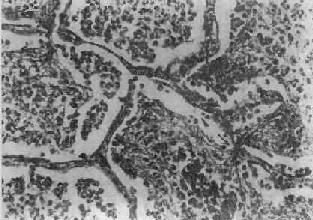

图9-15 大叶性肺炎

肺泡腔内充满纤维素性渗出物,纤维素丝穿过肺泡间孔,使相邻肺泡内的纤维素网互相连接